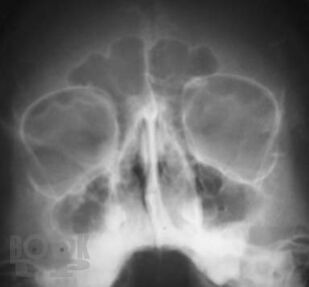

Рентгенографическая и компьютерно-томографическая диагностика острых и хронических синуситов

Монография посвящена применению классической рентгенографии и рентгеновской компьютерной томографии для диагностики острых и хронических воспалительных заболеваний околоносовых пазух. Результаты обоих исследований сопоставлены между собой по разработанной авторами методике, предложены адаптированные к практической работе подходы к обоснованному выбору указанных методов рентгенодиагностики синуситов. Книга хорошо иллюстрирована, содержит примеры описания рентгенограмм и компьютерных томограмм околоносовых пазух.